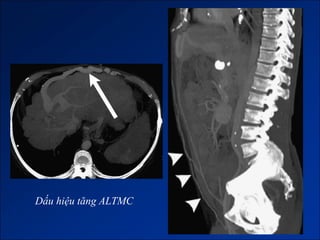

Dấu hiệu tăng ALTMC

2. Dấu hiệu tăng ALTMC